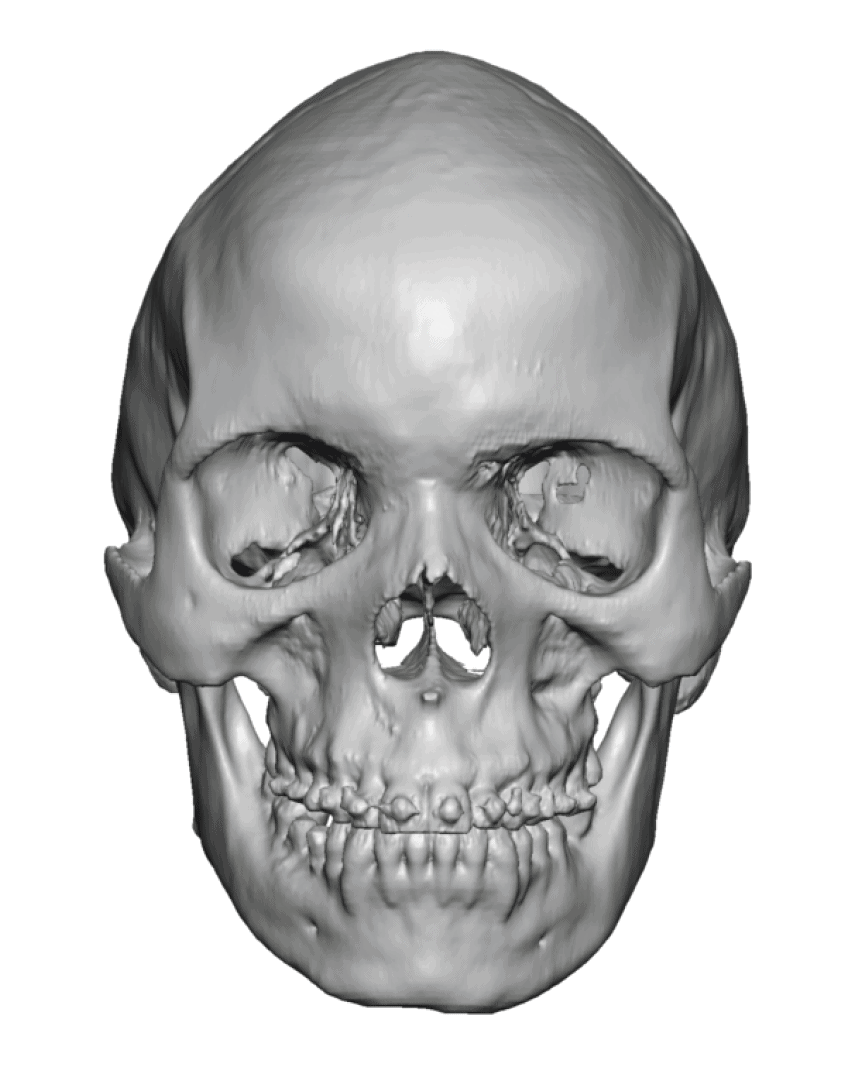

Patient 51

Desire for taller and rounder head shape.

Two stage custom skull implant augmentation technique.

Desire for taller and rounder head shape.

Two stage custom skull implant augmentation technique.